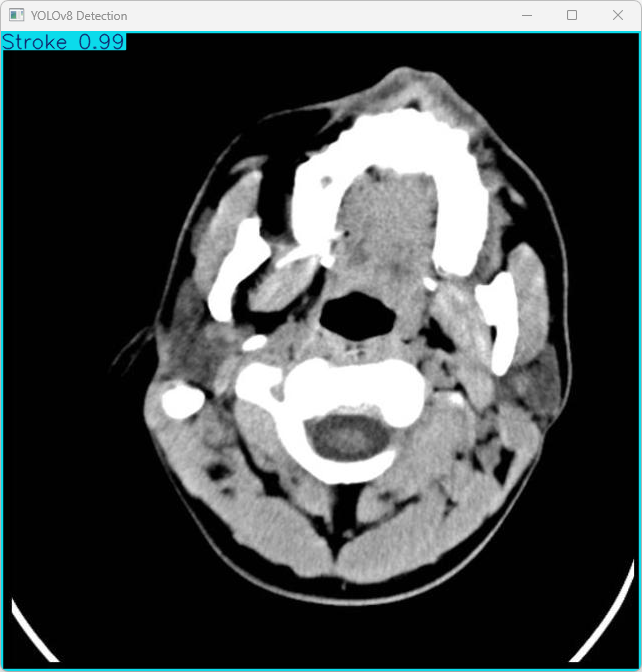

执行imgTest.py代码后,会将执行的结果直接标注在图片上,结果如下:

这段输出是基于YOLOv8模型对图片“imagetest.jpg”进行检测的结果,具体内容如下:

图像信息:

(1)处理的图像路径为:TestFiles/imagetest.jpg。

(2)图像尺寸为640×640像素。

检测结果:检测到 1 个 Stroke(中风)

处理速度:

(1)预处理时间: 5.0 毫秒

(2)推理时间: 9.0 毫秒

(3)后处理时间: 73.8 毫秒

总结:

系统成功检测到图像中的中风特征,整体处理时间为 87.8ms,符合快速检测的需求,结果已保存至指定目录,便于后续验证和应用。